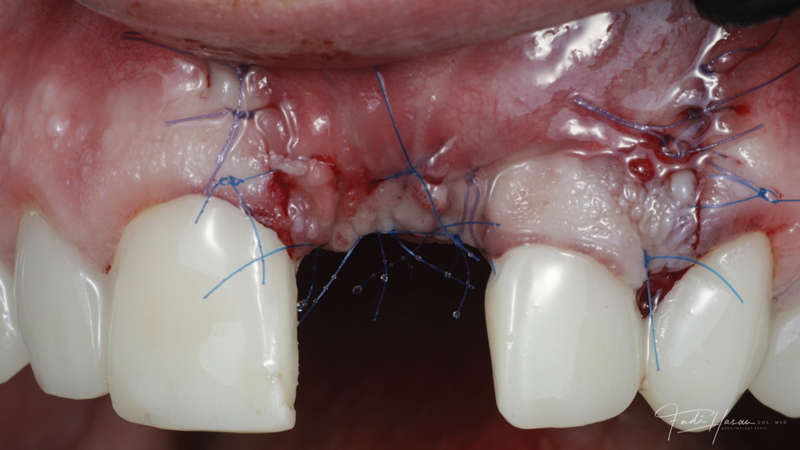

(8.) The flap was coronally positioned and sutured into place.

Figure 8